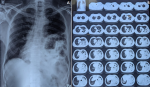

A 60-year-old man presented to the emergency department with an 8-day history of progressive breathlessness. He reported a head-on motor vehicle collision 10 years earlier but remained asymptomatic and was never evaluated at that time. Clinical examination revealed markedly reduced air entry over the left hemithorax, with audible bowel sounds in the same region. Chest radiograph (image A) and high-resolution computed tomography (HRCT) thorax (image B) demonstrated a large ~5.8 cm posterolateral defect in the left hemidiaphragm, consistent with a Bochdalek hernia, with herniation of the stomach and small bowel loops into the left thoracic cavity. Associated rightward mediastinal shift and mild compressive atelectasis of the left lung were noted. The patient underwent prompt surgical repair with complete relief of symptoms. This case highlights the need for thorough evaluation following thoracoabdominal trauma-even in asymptomatic individuals-and reinforces that delayed presentation of traumatic Bochdalek hernia, though rare in adults, is a surgical emergency due to the risk of incarceration and strangulation.

Figure 1: A) chest X-ray showing herniation of the stomach and small bowel loops into the left thoracic cavity with rightward mediastinal shift; B) high-resolution computed tomography of the thorax showing ~5.8 cm posterolateral defect in the left hemidiaphragm